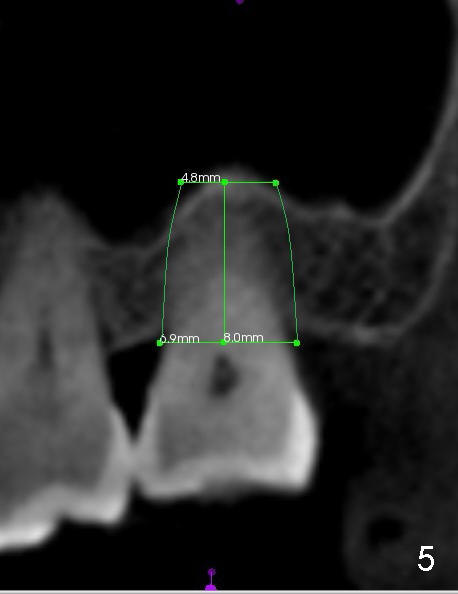

When the buccal roots are fused, there are 3 potential sites for immediate implant (Fig.1'): septum (*), buccal (B) and palatal (P) sockets. Septal placement (6.9x8 mm bone level implant) is the most ideal for restoration (Fig.3). The length of the implant can be increased (10 mm) with sinus lift so that the base of the implant between the buccal and palatal apices in height (Fig.4). Primary stability is derived mainly from the implant body engagement into the septum (Fig.5 coronal section through the septum). If bone density in the septum is high, a small implant may be appropriate (Fig.6,7: 6.4x8 mm). The large implant (6.9 mm) is chosen so that amount of bone graft to be used (Fig.8 red circles) is less.